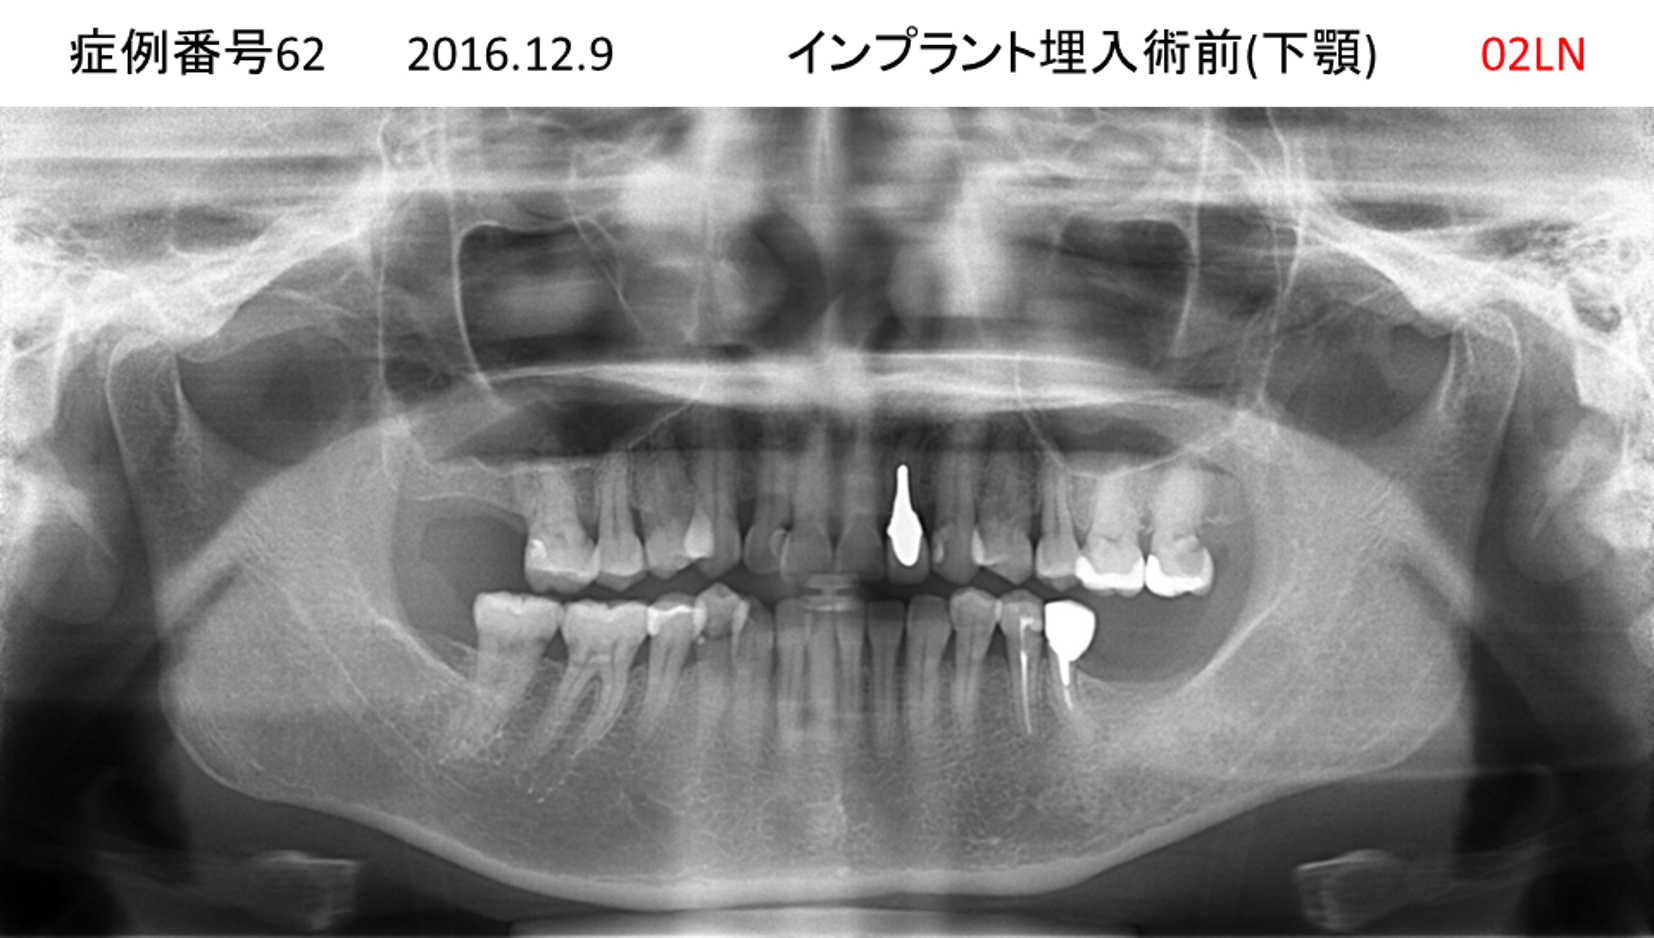

左下の歯が痛い患者様のインプラント症例

| 治療名称 |

インプラント |

| 治療費用 |

330万円+税 |

| 治療期間 |

4か月 |

| 患者さんの症状(主訴) |

左下の歯が痛い |

| 治療内容 |

サイナスリフト 抜歯即時インプラント |

| 治療結果 |

食事に困らない。見た目がとても良くなった。 |

| 治療の注意点(リスク/副作用) |

インプラントが壊れたら再治療が必要 |